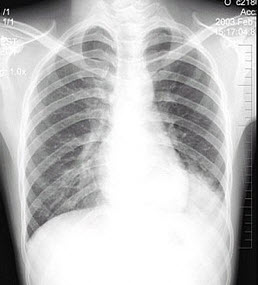

男性患者,19岁,咳嗽、发热1周,X线检查如图,最可能的诊断是( )

A:左下肺不张

B:左侧胸膜肥厚

C:左下肺炎症

D:左侧胸腔积液

E:左下支气管扩张